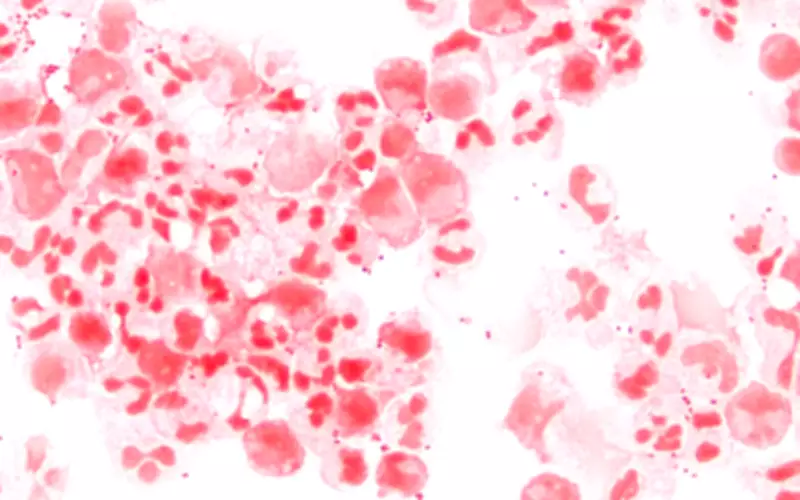

A meningite é uma inflamação das meninges, que são as membranas que envolvem todo o sistema nervoso central. Essa condição pode ser causada por micro-organismos como bactérias e vírus, além de alergias a medicamentos, câncer e outros agentes. Embora os sintomas iniciais possam ser confundidos com os de uma gripe comum, as sequelas da meningite são graves e a doença pode ser fatal.

Além da alta taxa de mortalidade, as complicações incluem surdez, perda dos movimentos e danos ao sistema nervoso. As crianças representam a faixa etária mais afetada, e os pacientes geralmente necessitam de acompanhamento médico por pelo menos seis meses após o diagnóstico. No Brasil, a meningite é considerada uma doença endêmica, com casos ocorrendo ao longo de todo o ano.

Transmissão e sintomas da meningite bacteriana

Conforme explica o Ministério da Saúde, a meningite pode ser causada por bactérias, vírus, fungos e parasitas. A transmissão ocorre quando pequenas gotas de saliva de uma pessoa infectada entram em contato com as mucosas do nariz ou da boca de um indivíduo saudável, por meio de tosse, espirro ou secreções respiratórias. É importante ressaltar que essa transmissão requer contato direto, íntimo e frequente com a pessoa doente.